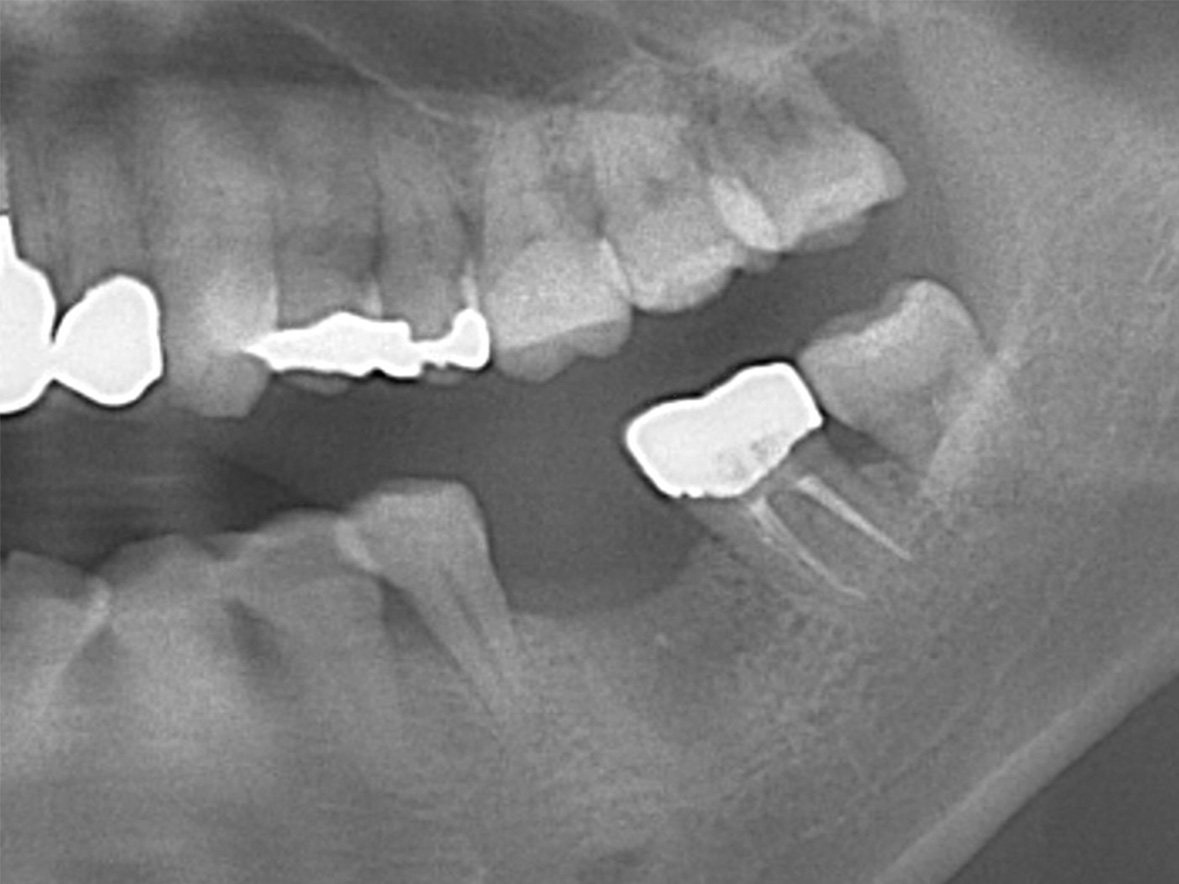

症例5

患者様の年齢 30代男性 主訴 差し歯取れた 治療内容 右下7インプラント治療

GBR+抜歯即時インプラント埋入後4ヶ月の待機期間後、ジルコニアによる上部構造装着費用 50万円 治療期間・通院回数 3ヶ月/6回 デメリット・リスク 外科処置に伴う痛み・腫れ・出血・合併症の可能性があります。 -